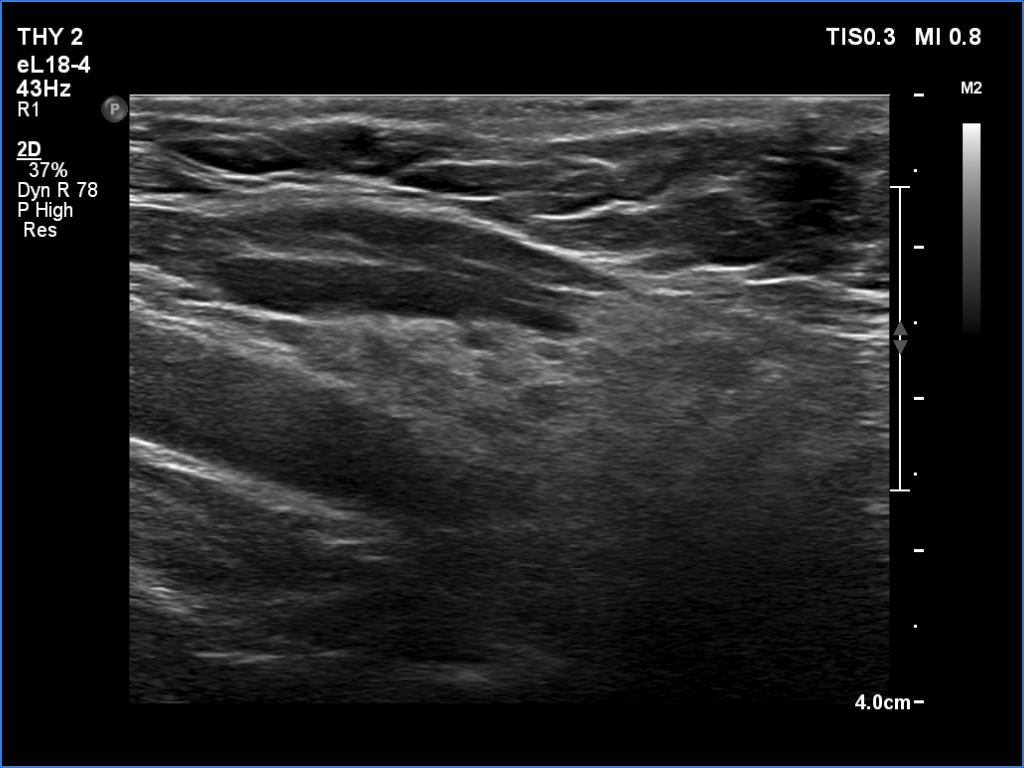

Lymphocytic thyroiditis - case 1441

Right lobe

Left lobe

Focal form of lymphocytic thyroiditis is presented. The thyroid has numerous discrete, hypoechoic lesions which correspond to more active foci of thyroiditis. The interpretation of the relatively large ventral hypoechoic area in the left lobe (right upper image can cause problem), however, longitudinal scan decides the issue: this field cannot be a pathological nodule.